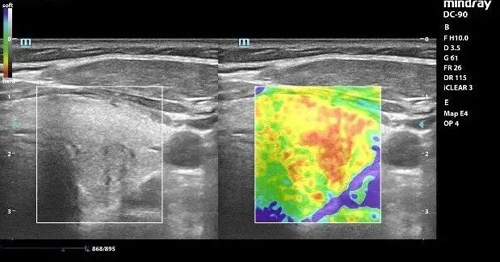

随着技术的进步,目前对甲状腺结节还可以进行弹性成像的评估以及造影的检查,对于甲状腺结节的诊断及治疗都有重要的意义。

弹性成像